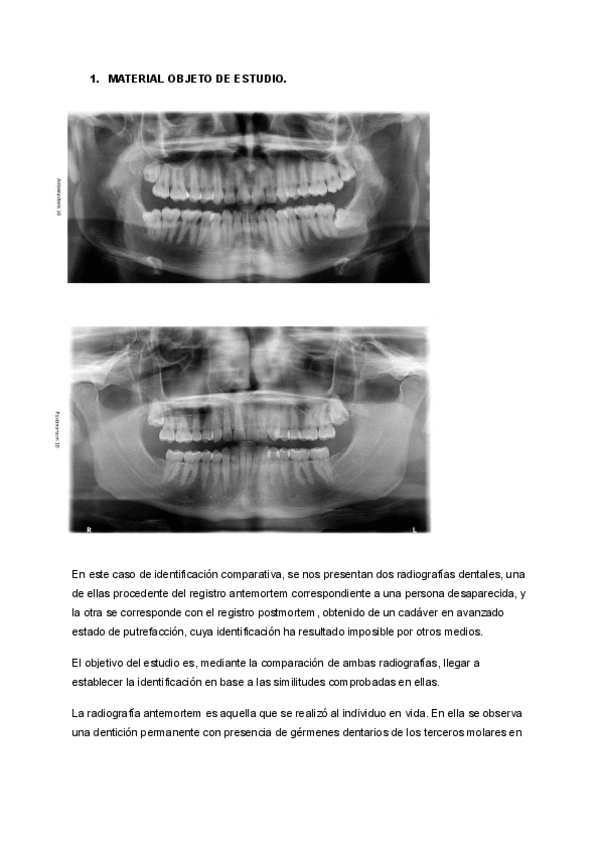

IDENTIFICACIÓN COMPARATIVA RADIOGRAFÍA

He publicado nuevos practicas de 1º Técnica Odontológica Forense: FORENSE-PRACTICA-1.pdf

IDENTIFICACIÓN A TRAVÉS DE LA QUEILOSCOPIA